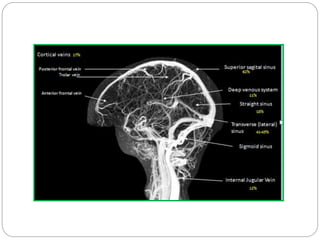

Major cerebral veins and sinuses